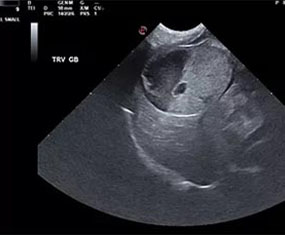

At RVUS we have chosen industry leading equipment from vendors with reputable and proven track records in the industry. From the front lines to your final report it is imperative that the equipment and the user provide images that equip the specialists with the highest level of quality and reproducibility to confidently provide an accurate interpretation of the sonogram.

This, in turn, provides you with additional tools to arrive at a diagnosis and prognosis and to enhance the care model for your patient and confidence with your client. Our team of professionals with decades of ultrasound experience encourage the use of ultrasound as a leading route to non-invasively assess organs and pathology in question. To cover that spectrum, a variety of transducers are essential, all with different characteristics.

Whether your patient is 100 lbs or 10 lbs, take comfort in knowing your sonographer is capable of generating images that are sensitive and specific to the clinical concerns.